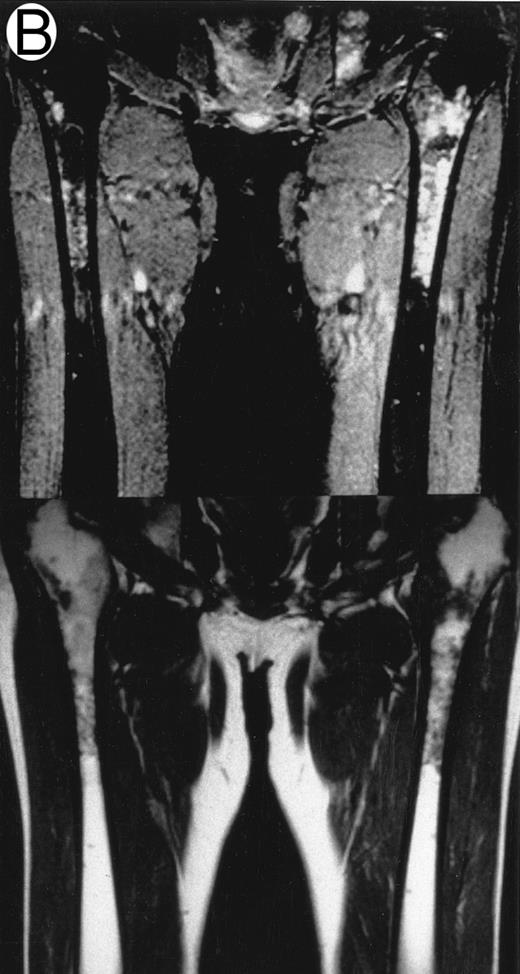

MRI.MRI was performed using SE sequences with the whole-body coil in a 1.5 tesla superconducting system (MRT 200FX/II; Toshiba, Tokyo, Japan). Coronal T1-weighted SE images of the femur were obtained in contiguous 10-mm slices in a 256 × 256 matrix with TR, 400 ms; TE, 20 ms; and number of signal acquisitions, 2. Tissues with short proton T1, such as fatty tissue, have a high signal intensity and appear bright on T1-weighted SE images, whereas those with a long T1, such as cellular marrow, have a low signal intensity and appear dark. STIR coronal images of the femur were obtained in 10-mm slices in a 256 × 256 matrix with TR, 1,500 ms; TE, 20 ms; and TI, 150 ms. On STIR images, the signal from fatty tissue is eliminated, whereas the signal from tissues with a longer T1 is progressively brighter. The MRI results were evaluated blindly by two independent observers who had no knowledge of the patients' marrow histology, tumor type, or stage. The MRI was classified as positive when both observers classified the T1-weighted SE images and STIR images as abnormal. The positive findings on femoral marrow MRI were categorized as follows: nodular pattern, characterized by nodular areas of fatty marrow replacement with a signal intensity that was lower on T1-weighted SE images (higher on STIR images) than that of muscles; scattered pattern, characterized by multiple scattered foci of marrow replacement on a background of uninvolved marrow; and uniform pattern, characterized by a uniform replacement of fatty marrow (Fig 1).

Patterns observed on femoral marrow MRI. (A) Nodular (arrow), (B) scattered, and (C) uniform. Top: STIR images and, bottom: T1-weighted SE images.

MRI patterns of femoral marrow.MRI findings of the femoral marrow were classified into three patterns as shown in Fig 1. Of 29 patients with a positive MRI, 21 (72%) exhibited a scattered pattern (Fig 1A), 6 patients (21%) demonstrated a uniform pattern (Fig 1B), and 2 patients (7%) exhibited a nodular pattern (Fig 1C). Of the 17 patients with positive results on BM biopsy, 11 demonstrated a scattered pattern on the MRI, and 6 patients showed a uniform pattern.